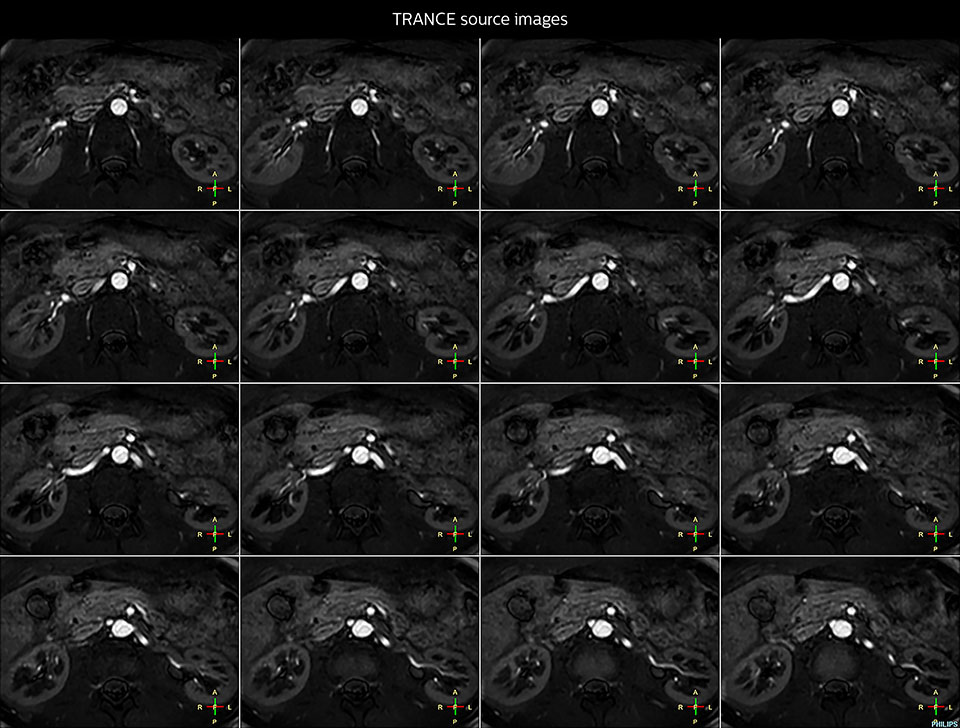

Non-contrast MRA of renal arteries

Imaging the renal arteries without contrast agent on Prodiva 1.5T.